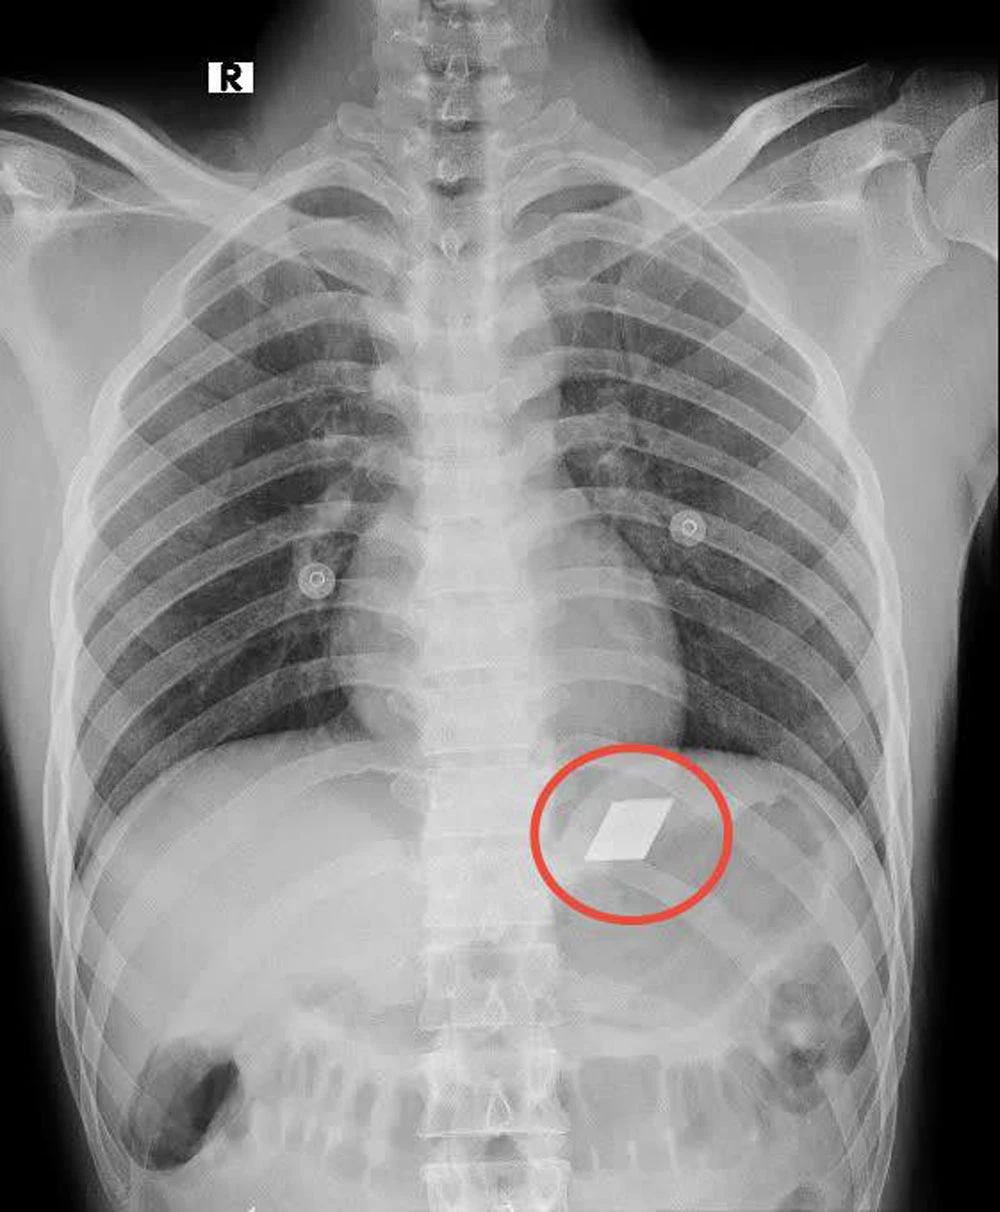

Lưỡi dao rọc giấy và dao lam nằm trong bụng nam bệnh nhân được các bác sĩ gắp thành công ra ngoài. Ảnh: BV

Đại diện Bệnh viện Đa khoa tỉnh Bình Dương cho biết bệnh nhân L (26 tuổi), nhập viện trong tình trạng đau bụng dữ dội và khó thở. Sau khi siêu âm, các bác sĩ phát hiện phát hiện có dị vật sắc nhọn nằm trong thực quản và dạ dày của bệnh nhân.

Ngay lập tức, các y bác sĩ đã họp để chẩn đoán và đưa ra phương án can thiệp khẩn cấp. Sau đó, các bác sĩ đã tiến hành nội soi dạ dày. Tiếp đến, các bác sĩ đã dùng phương pháp nội soi để gắp một nửa dao lam đang bị kẹt ở miệng thực quản. Đồng thời, gắp 4 mảnh lưỡi dao rọc giấy ra khỏi dạ dày của bệnh nhân.